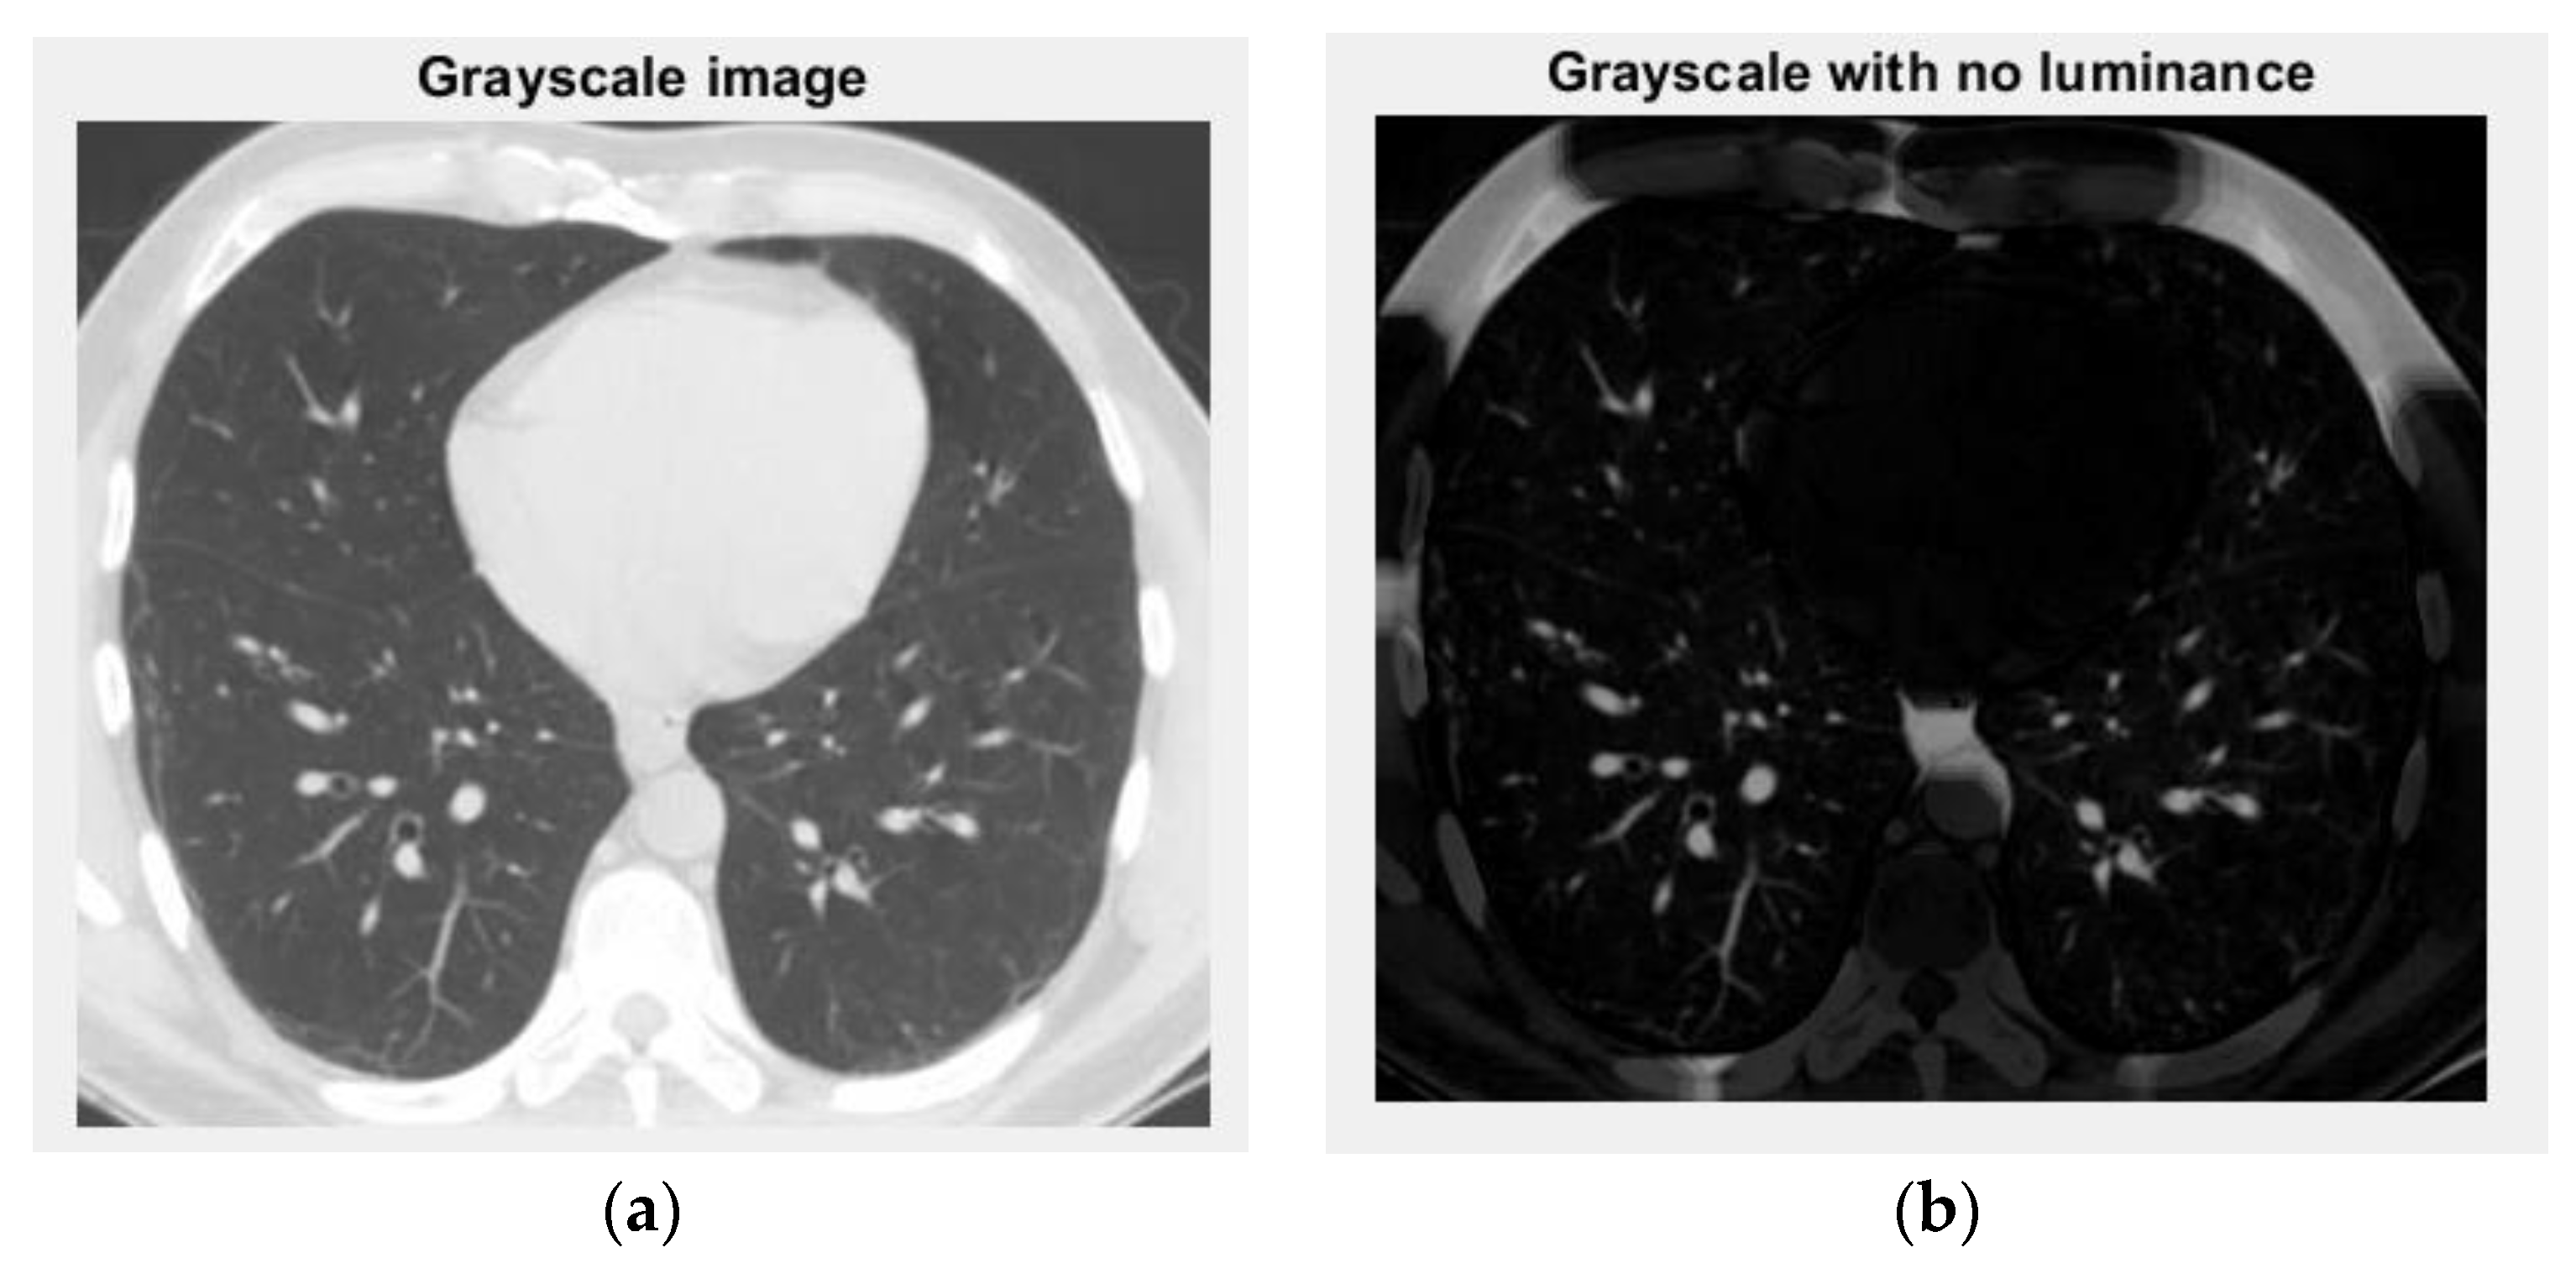

Figure 20 and Figure 21 are the grayscale images with and without luminance of the non-COVID-19 lung CT image, respectively, the filtered versions of the non-COVID-19 lung CT image.

Figure 20. Grayscale versions of the non-COVID-19 lung image: (a) grayscale image and (b) grayscale with no luminance.